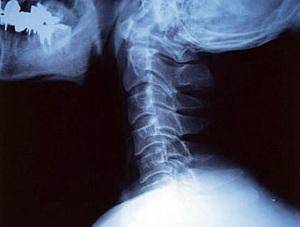

Грыжа шейного отдела позвоночника встречается относительно редко, но представляет для человека наибольшую опасность. В связи с близким расположением патологии к головному мозгу, есть риск нарушения мозгового кровообращения, вплоть до инсульта, потому как только диагностируется грыжа, начинается лечение. Для лечения шейного отдела позвоночника специалисты применяют комплексный подход: физиотерапия, мануальное лечение, медикаментозный курс, аппаратные методики и домашнее лечение народными средствами. На сегодня уже известно, что наиболее действенный метод – этиологическое лечение, которое позволяет устранить недуг без операции и на продолжительное время. Устранение причинного фактора направлено на восстановление позвоночника и предупреждение дальнейшего формирования патологии шейного отдела, а также для улучшения трофики хрящевой ткани и укрепления мышечно-связочного аппарата.